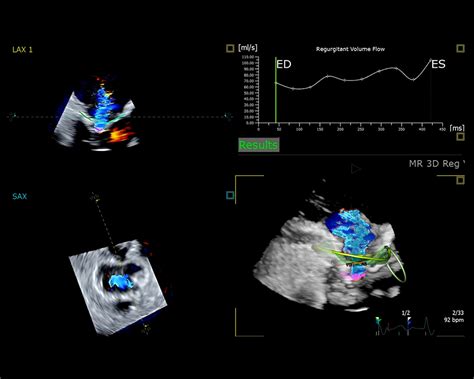

Najrozšírenejším využitím ultrazvuku je sonografia, metóda ultrazvukového zobrazovania, ktorá sa používa najmä v pôrodníctve na vyšetrovanie zdravia nenarodeného dieťaťa. Pomáha pri hodnotení gestačného veku, životaschopnosti plodu, umiestnenia placenty a detekcii fyzických abnormalít. Ultrazvuk sa tiež používa na zobrazovanie mäkkých tkanív, detekciu nádorov, analýzu štruktúry kostí a sledovanie prietoku krvi pomocou Dopplerovej techniky.